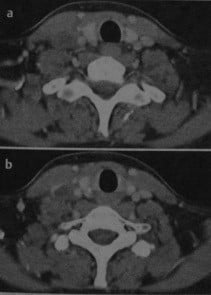

Анатомия внутренней яремной вены: КТ изображения